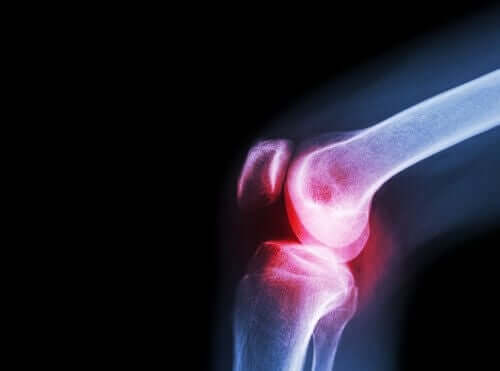

A artrite reumatoide é uma doença inflamatória crônica de natureza autoimune. Caracteriza-se por afetar muitas articulações e pelo desenvolvimento de vários sintomas gerais e não específicos.

Em relação aos sintomas, a artrite reumatoide se manifesta tipicamente com dor e rigidez, ou dificuldade de movimento nas diferentes articulações pequenas e grandes.

Essa é outra doença para a qual o aceclofenaco é indicado, pois é outra patologia reumática que lesiona a cartilagem das articulações.

No interior das articulações, há um fluido conhecido como líquido sinovial que é produzido pela membrana sinovial. As extremidades dos ossos que se unem para formar a articulação são revestidos pela cartilagem articular.

Quando essa cartilagem é lesionada, há dor, rigidez e incapacidade funcional. É importante diferenciar essa doença da artrite. Esta última se desenvolve por causa de uma inflamação da articulação, e não pelo desgaste da cartilagem.